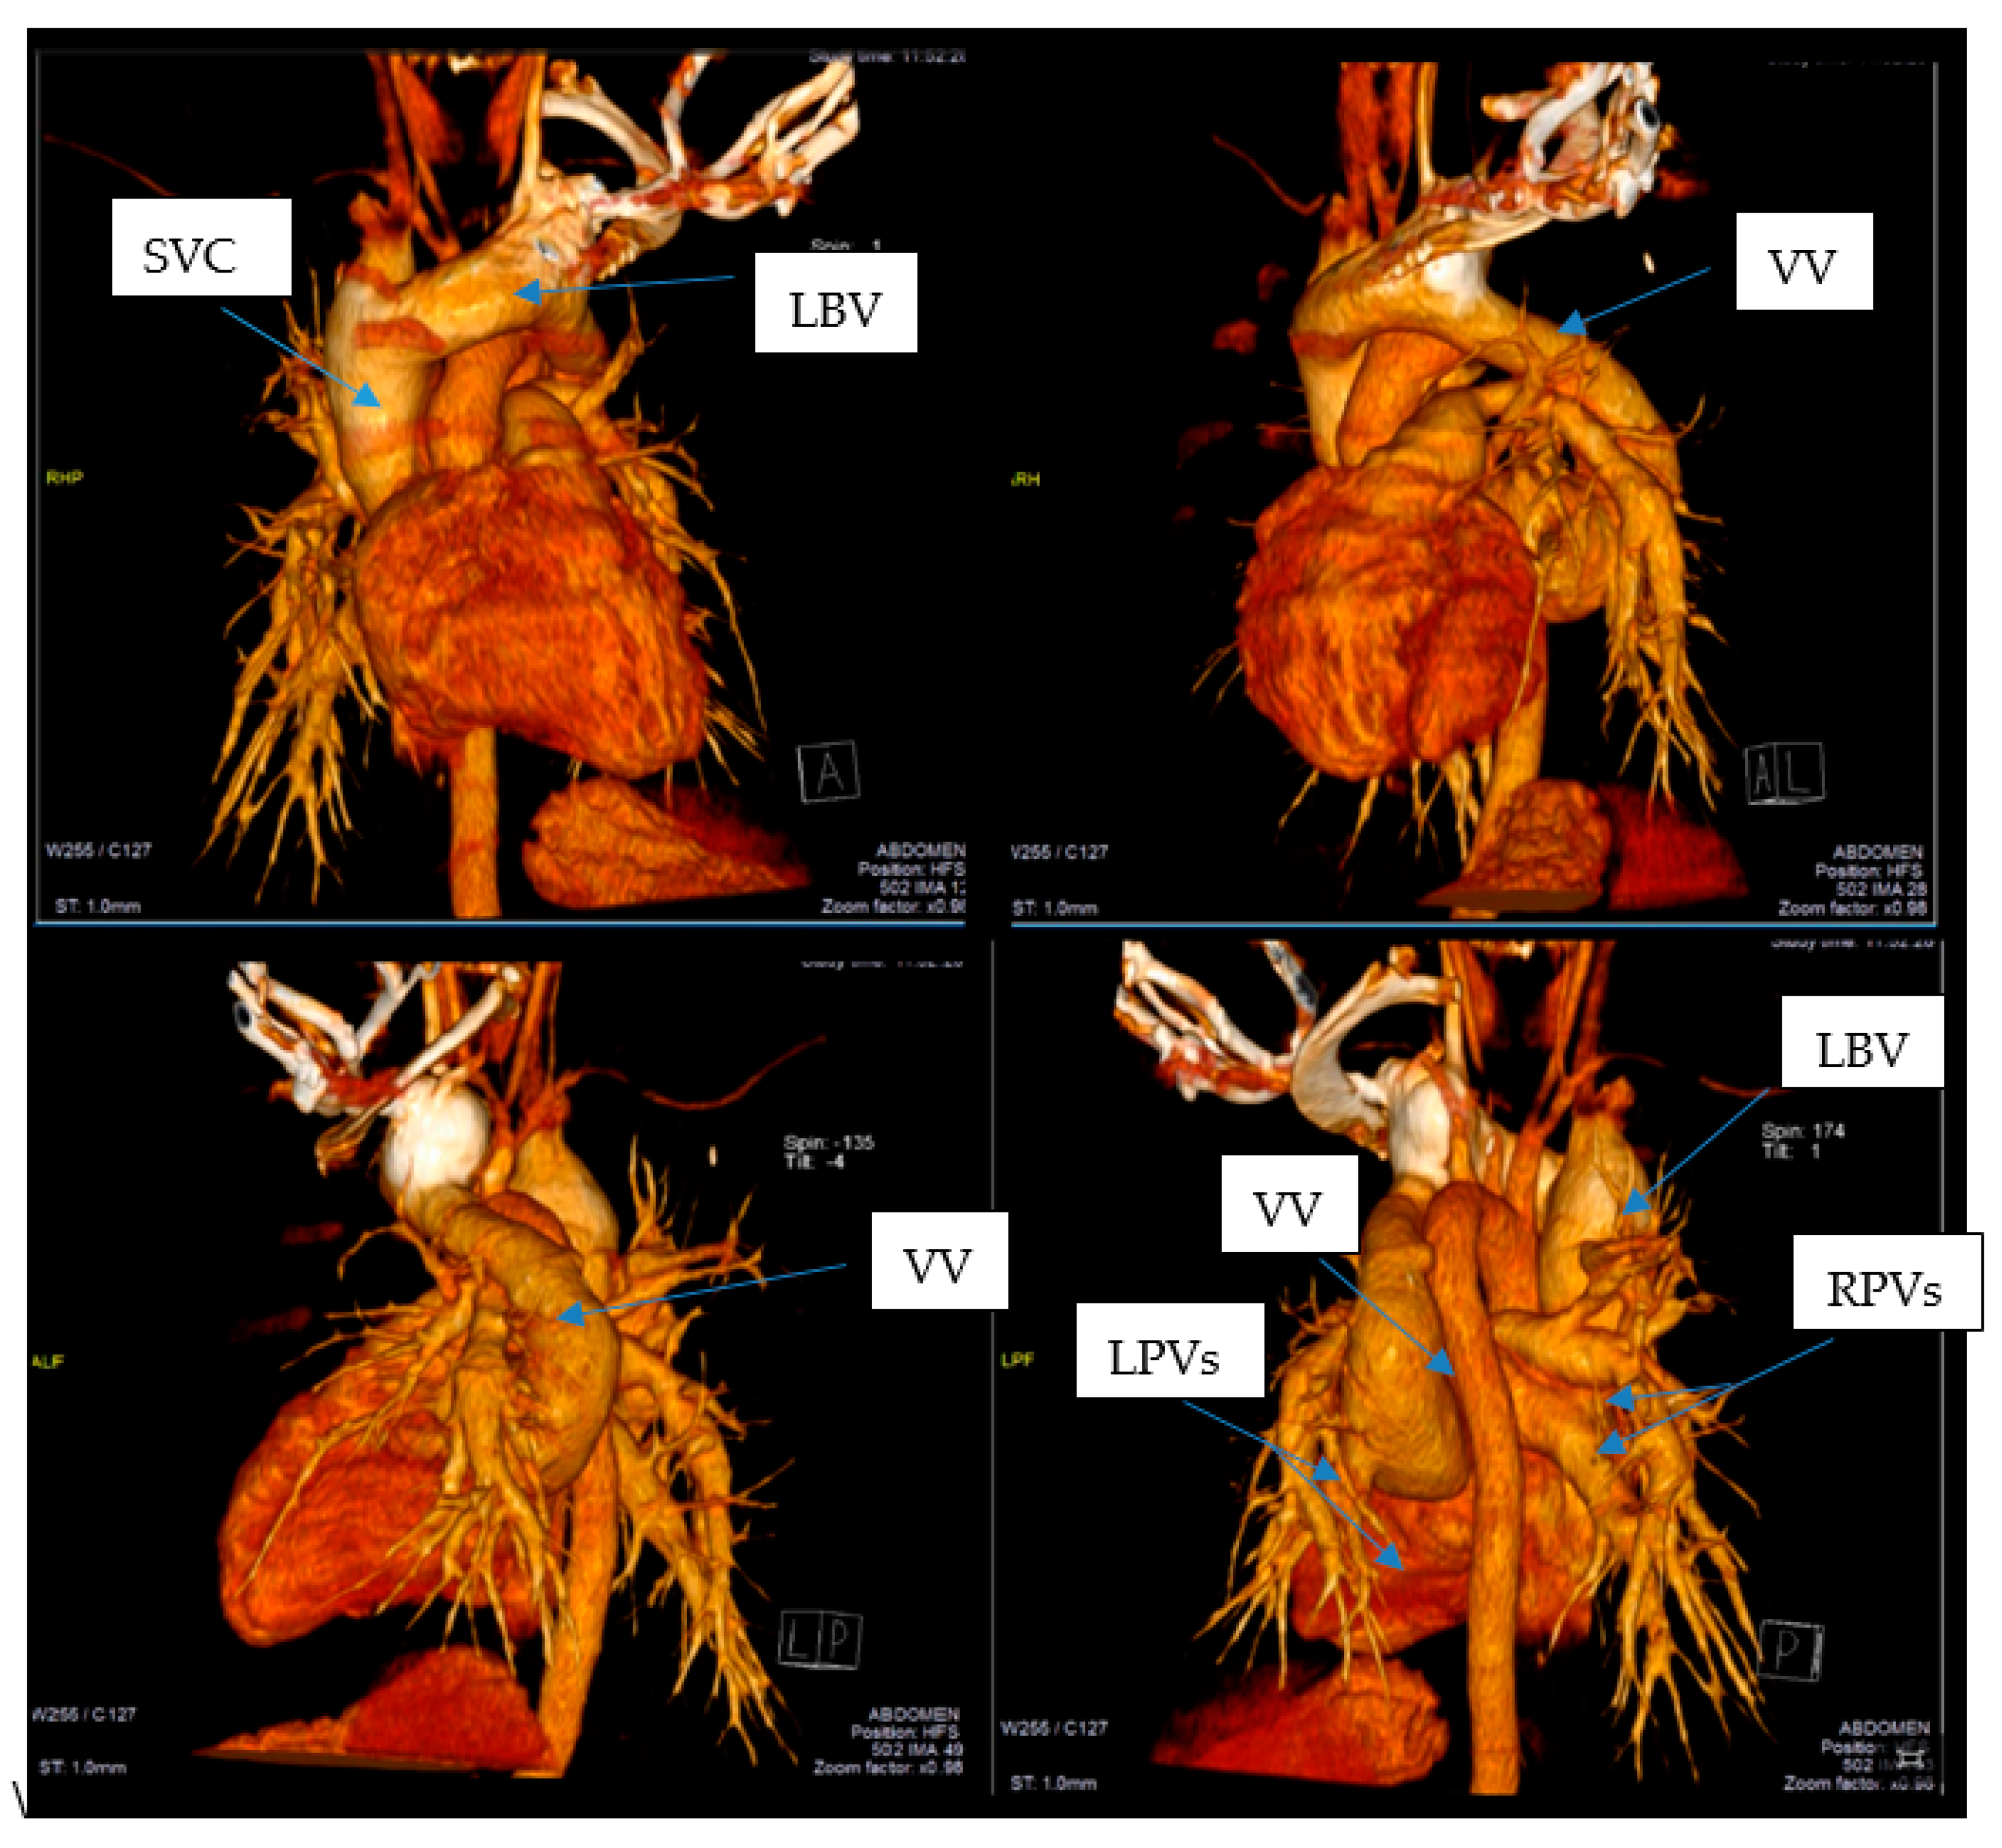

This led to further investigations and a thoracic CAT scan was performed. The thoracic CAT scan showed a vertical collecting canal (vein) located in the left side of the mediastinum that was considered to be a persistent left superior vena cava associated with an anatomical variation of the pulmonary venous return (Figure 1A,B). Upon detailed exploration and reconstruction, images revealed that the pulmonary venous drainage takes place above the heart, and all four pulmonary veins are ending into a common collecting canal and then this trunk opens into the left brachiocephalic vein that drains into the superior vena cava (Figure 2). It was not noted a connection (opening) between the collecting canal and the left atrium. Upon a closer investigation and interpretation of the thoracic CAT scan images, the patient was seen to have an atrial septal defect, and therefore oxygen rich blood was sparse due to a right-to-left shunt and drains blood into the left atrium (Figure 3).

Given the fact that in our case the four pulmonary veins were highlighted at the initial exploration, firstly it was considered that it was an anatomical variant of pulmonary venous return. It was considered that both left pulmonary veins join in a common trunk and two right pulmonary veins remain separate. The vertical collecting canal in the mediastinum was considered to be the persistence of the left superior vena cava. On a detailed re-examination and corroborated with the images of reconstruction and cardiac catheterization it was found that all four pulmonary veins do not open in the left atrium but they collect into a vertical canal (vein) that later opens into the left brachiocephalic vein, establishing diagnosis of a total anomalous pulmonary return. For a certain diagnosis it is very important to know these anatomical variants, as well as to establish the differential diagnosis with vascular development abnormalities.

Figure 2. All four pulmonary veins are ending into a collecting canal that opens into the left brachiocephalic vein that drains into the superior vena cava. SVC—superior vena cava; LBV—left brachiocephalic vein; VV—vertical vein; LPVs—left pulmonary veins; RPVs—right pulmonary veins. Arrows shows the great vessels related to the heart.